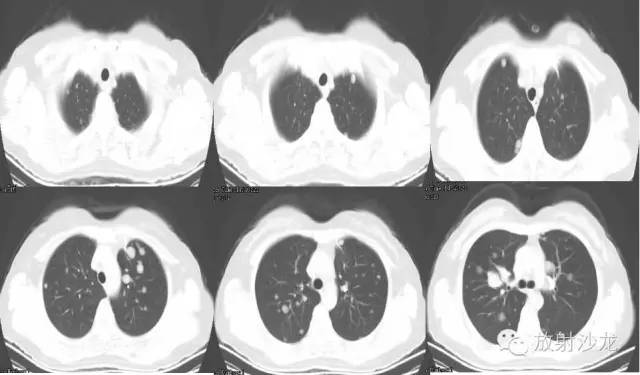

【影像表现】

双侧胸廓对称,纵隔居中。双肺可见散在多发大小不等类圆形软组织密度影,密度欠均,边界较清,最大者约5.32cm*7.88cm*6.75cm,右肺中叶、下叶可见一不规则形透亮影,内无肺纹理,纵隔未见明显肿大淋巴结,胸膜无增厚,右侧胸腔内可见弧形液体密度影。